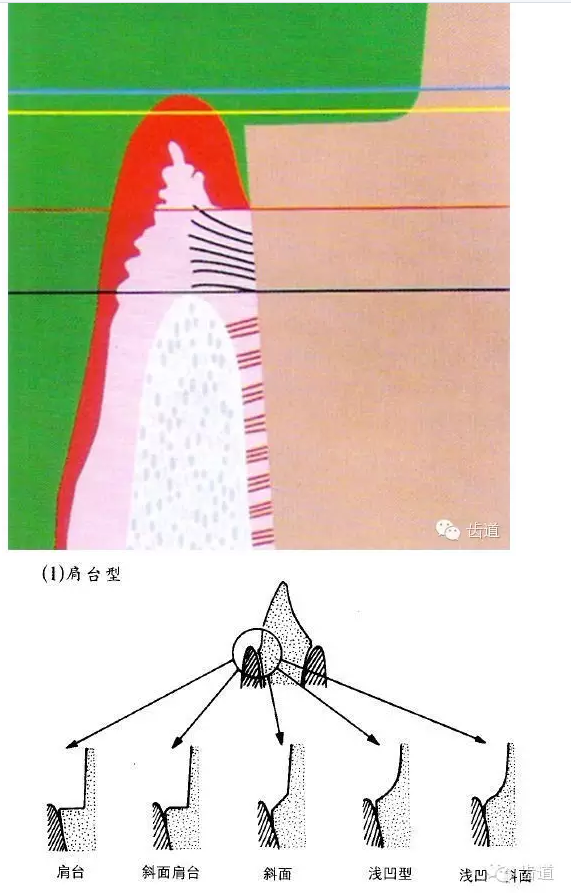

l邊緣的適合性